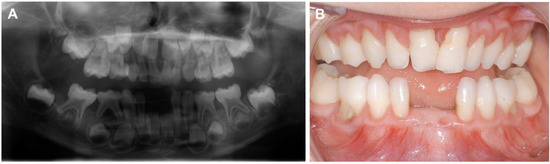

2. Case Report

2.3. Oral Examination